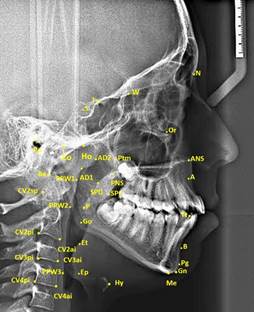

In study, 35 cephalometric points (Figure 1), 8 cephalometric planes, and 30 cephalometric measurements (Figure 2) were used. In the cephalometric analysis; 5 craniofacial, 8 nasopharyngeal, 7 oropharyngeal, 2 hypopharyngeal (Figure 3), 9 hyoid measurements (Figure 4) and 4 area measurements (Figure 5) were used.